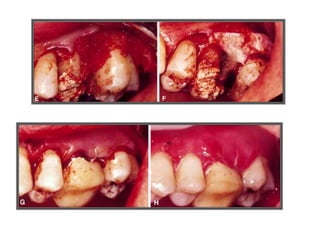

CASO 1

CASO 2

CASO 3

CASO 4

CASO 5

CASO 6